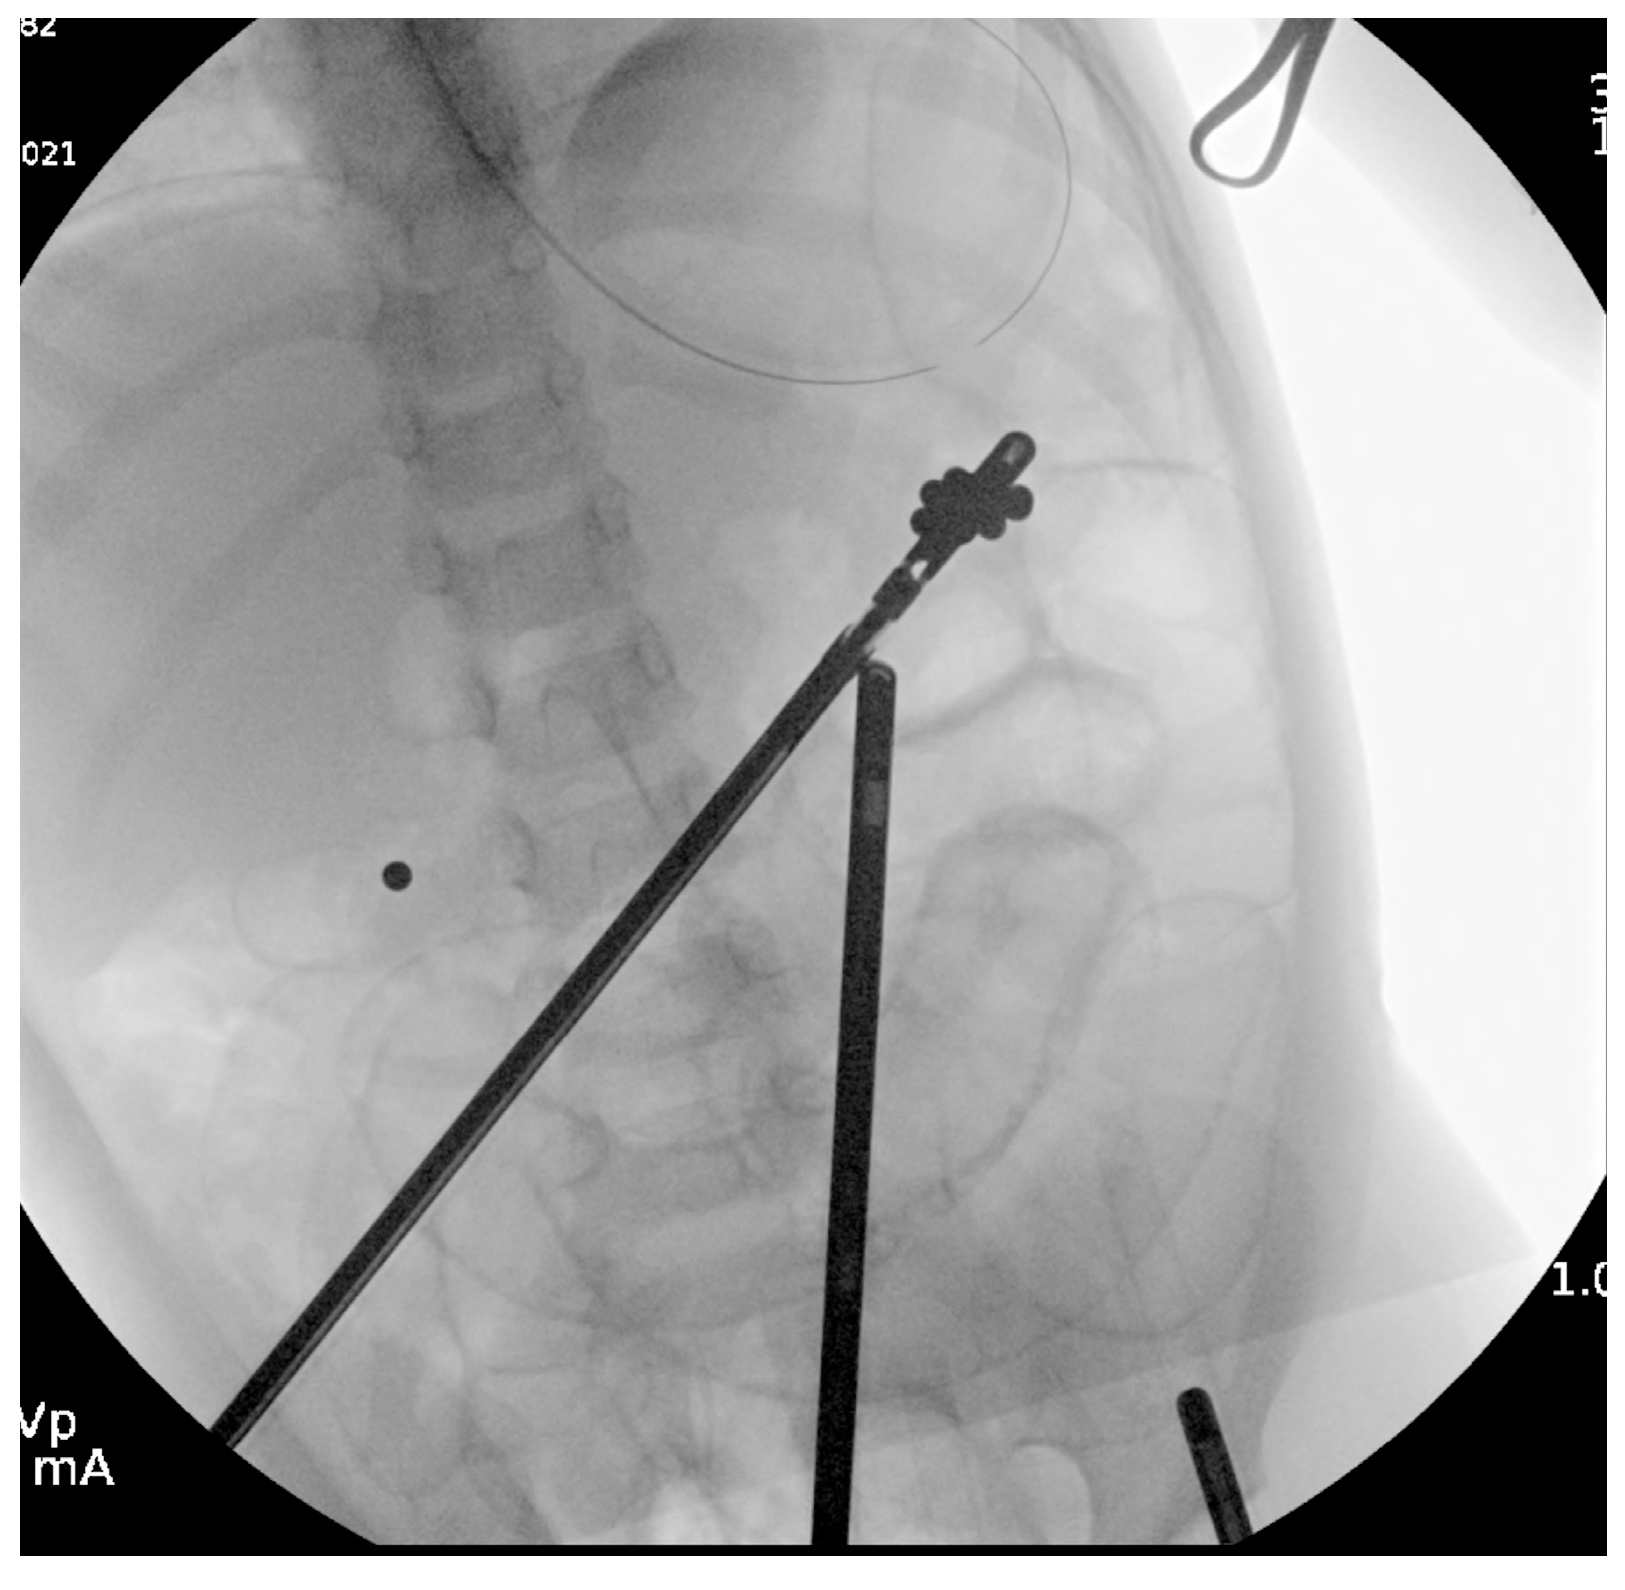

Interventions occurred across multiple anesthetic settings. Otolaryngology performed direct laryngoscopy, successfully removing two magnets adhered to the uvula with minimal trauma, consistent with findings from previous studies [4]. Gastroenterology then conducted an upper endoscopy, revealing a tightly clustered arch of 30 bb-sized magnets compressing the gastric incisura (Figure 2). Using a Roth net, they removed the magnets in two passes with no complications other than minor erosions on the gastric mucosa. Post-procedural imaging revealed residual magnets in the proximal jejunum (Figure 3).

Figure 2. A cluster of 30 bb-sized magnets was retrieved using a roth net in two passes. Superficial bb-sized erosions were noted on the proximal incisura.